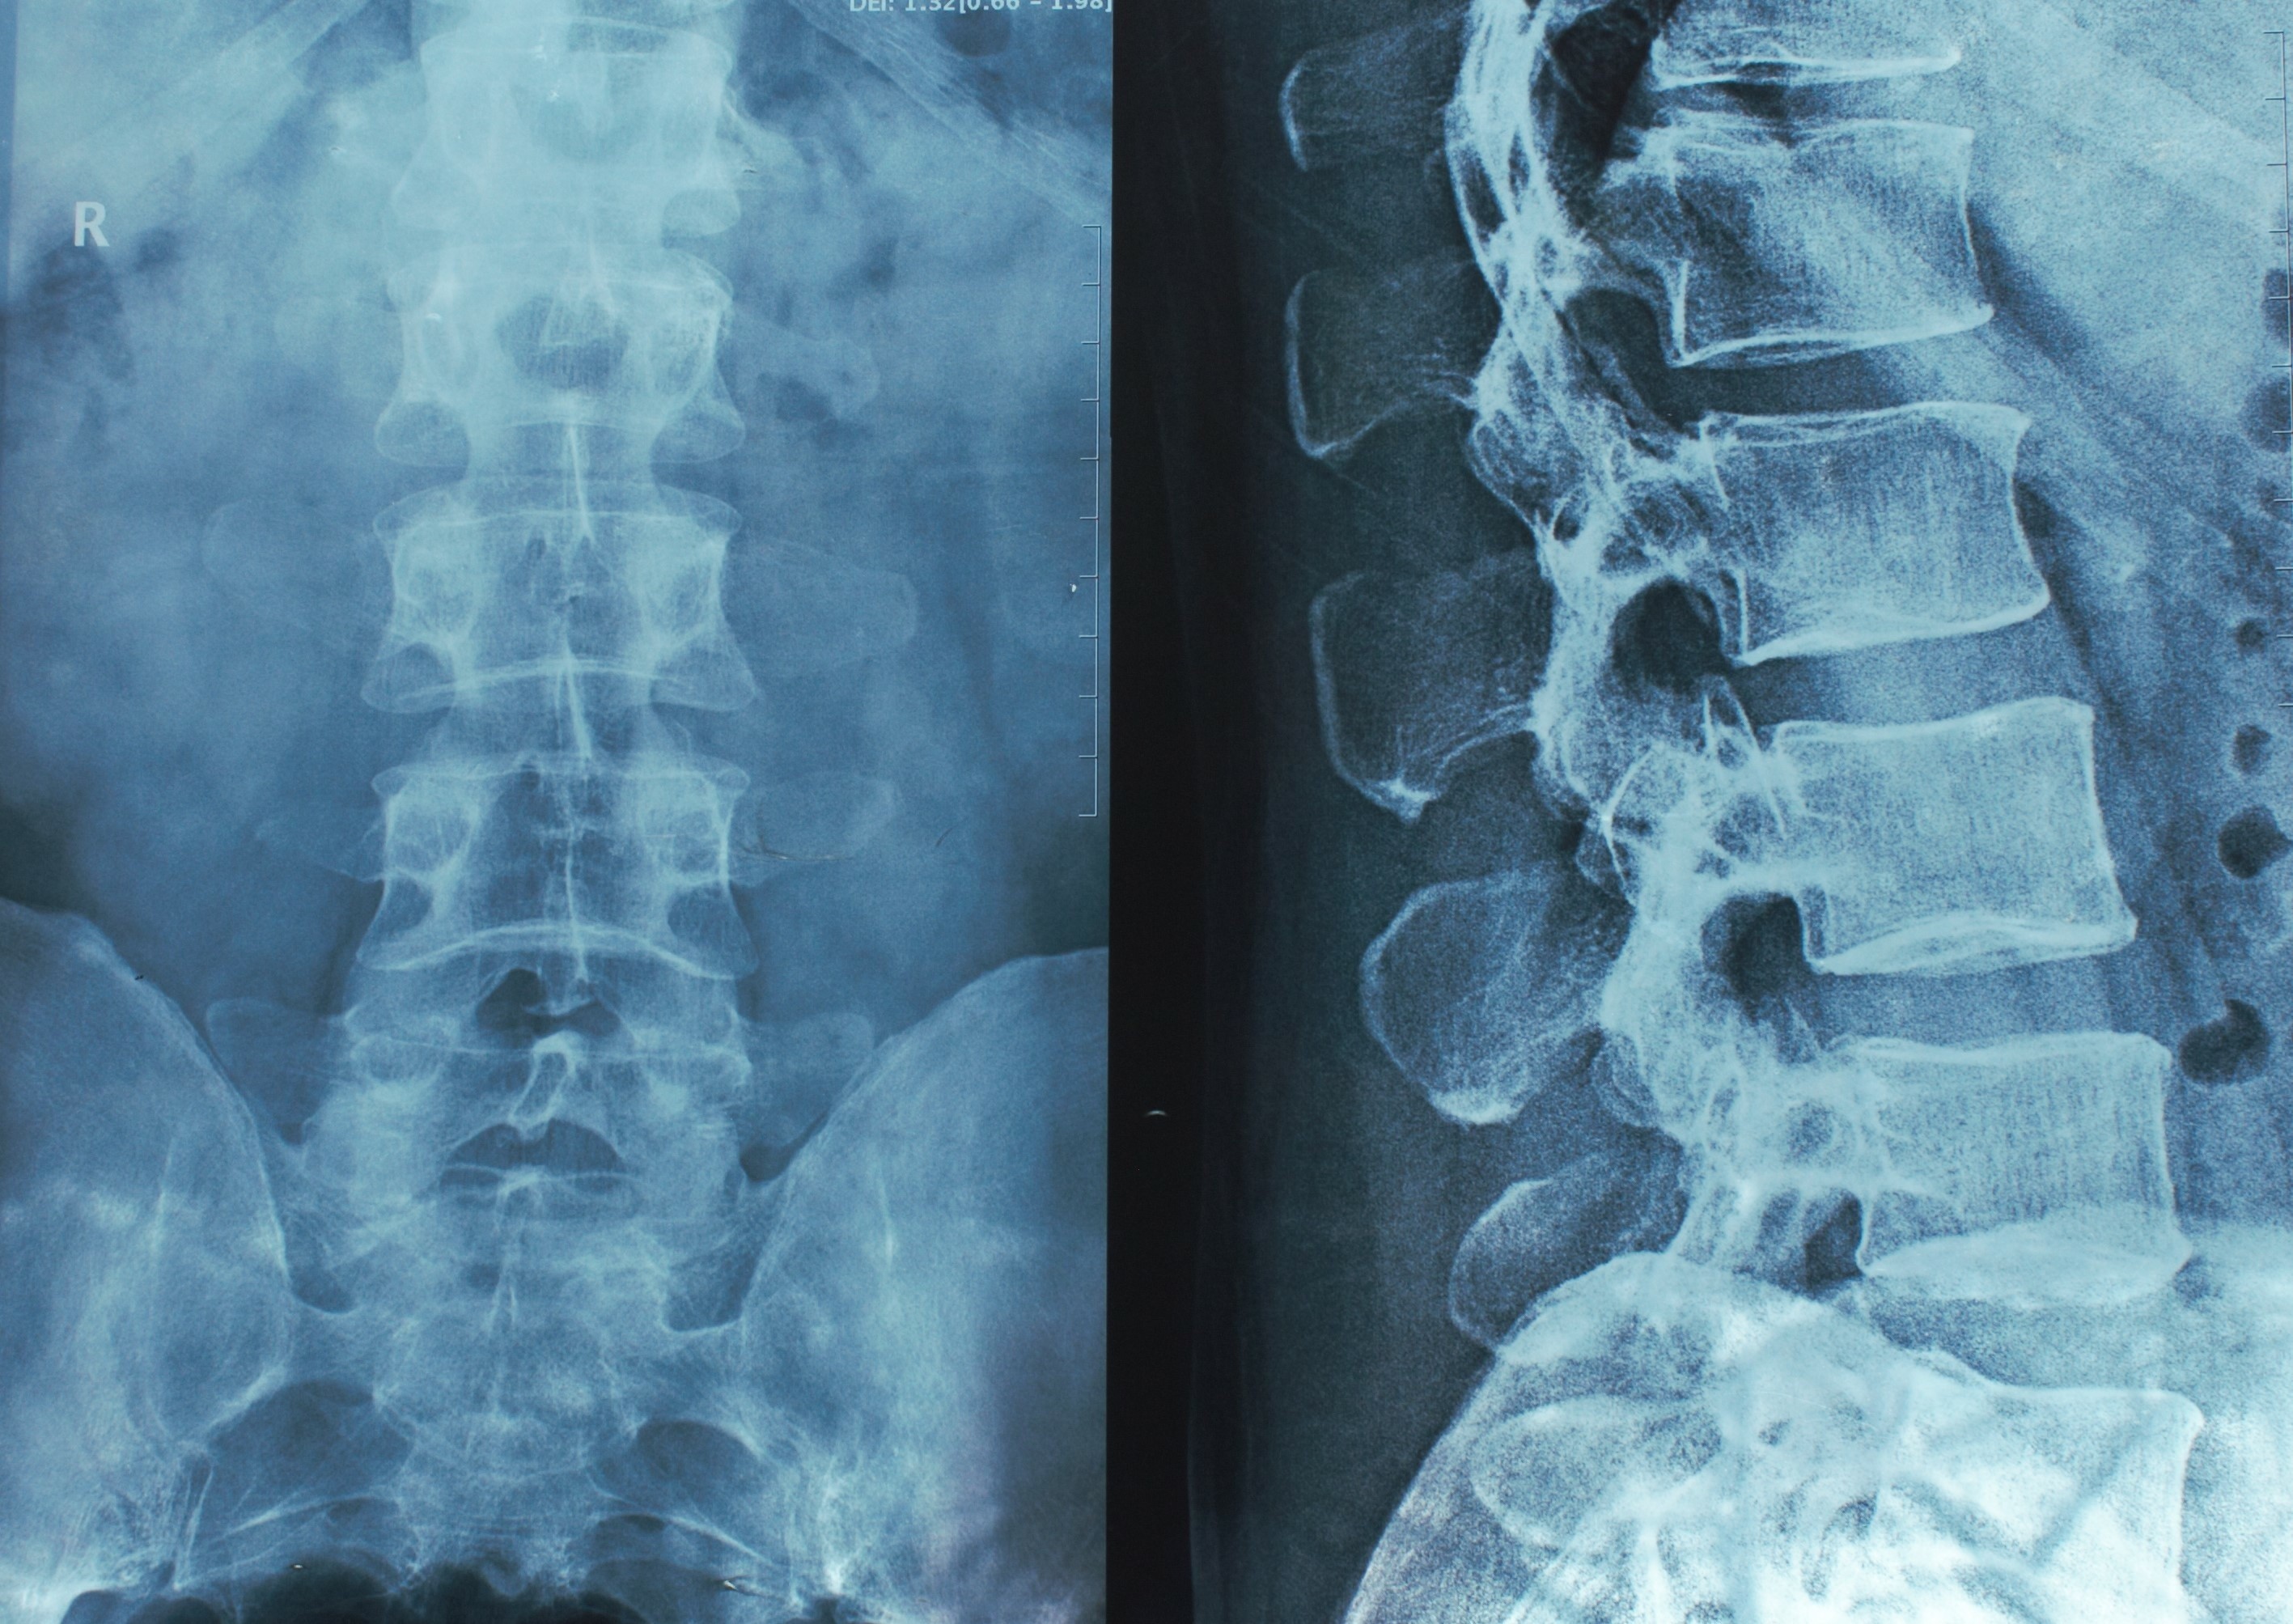

Spine care has traditionally relied on static snapshots of a patient’s condition. Radiographs, CT scans, and MRIs reveal anatomy and alignment, while Patient Reported Outcome Measures (PROMs) capture how a patient feels at a single point in time. These tools are helpful, but they only offer brief glimpses into real life. A supine MRI does not show the spine under load, and a standing X-ray captures a single position that may not reflect how a patient naturally moves or holds themselves throughout the day. PROMs provide valuable insight but are influenced by the patient’s mood, pain level, and the artificial setting of a clinic visit.

Adult spinal deformities (ASDs) make this gap clear. The core issue in ASD is dynamic dysfunction. As alignment worsens, patients rely on compensatory mechanisms such as pelvic tilt, knee flexion, and altered gait to maintain balance and reduce energy expenditure, often without noticing. Metrics like the sagittal vertical axis (SVA) and Pelvic Incidence - Lumbar Lordosis (PI–LL) describe static alignment, but they cannot reveal how the spine behaves in motion. Many patients who appear well aligned on X-ray still struggle with endurance, balance, or mechanical symptoms.

Surgeons have always recognized this disconnect. Two patients can share the same radiographic parameters and function completely differently. True assessment of spinal balance requires more than static imaging. It requires dynamic, objective insight into how patients move, compensate, and recover in their own environments.